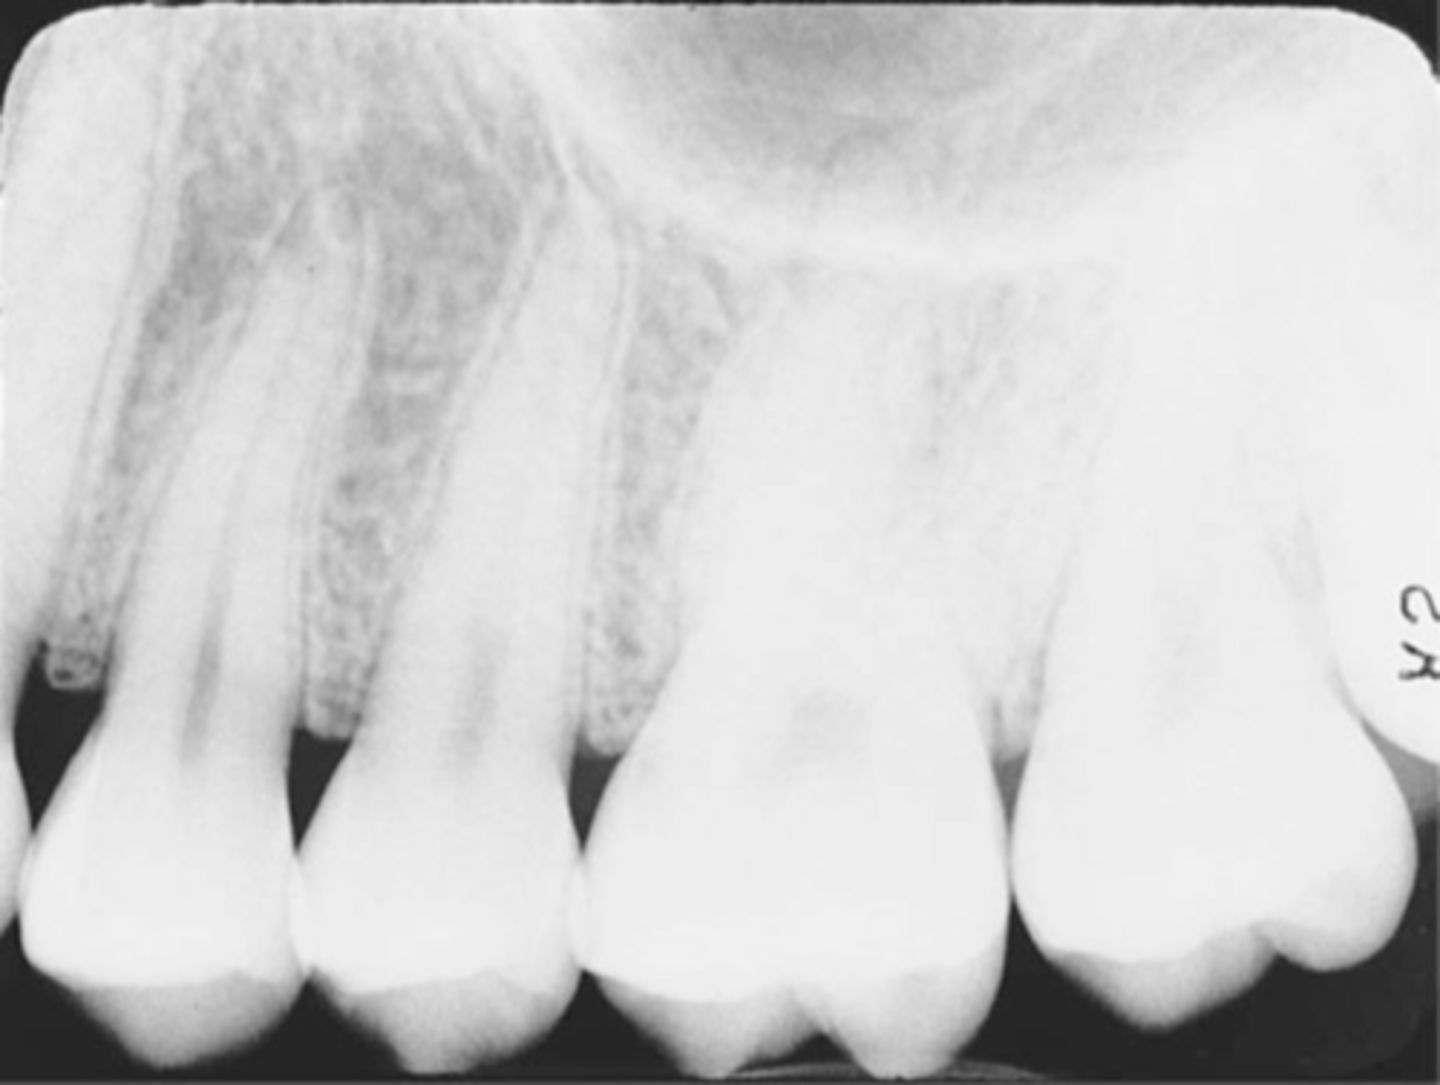

Incorrect Vertical Angulation-->Elongated Images

-Teeth appear long and distorted

-Vertical angulation was insufficient or too flat, resulting in images that are longer then the actual teeth.

-Occurs more often with the bisecting technique

-To prevent use adequate vertical angulation

Tube Head & PID-->Elongation of the Image

-Bisecting technique error

-Insufficient Angulation (not steep enough), causing elongation or increased anatomy of the teeth and cutting off apex.